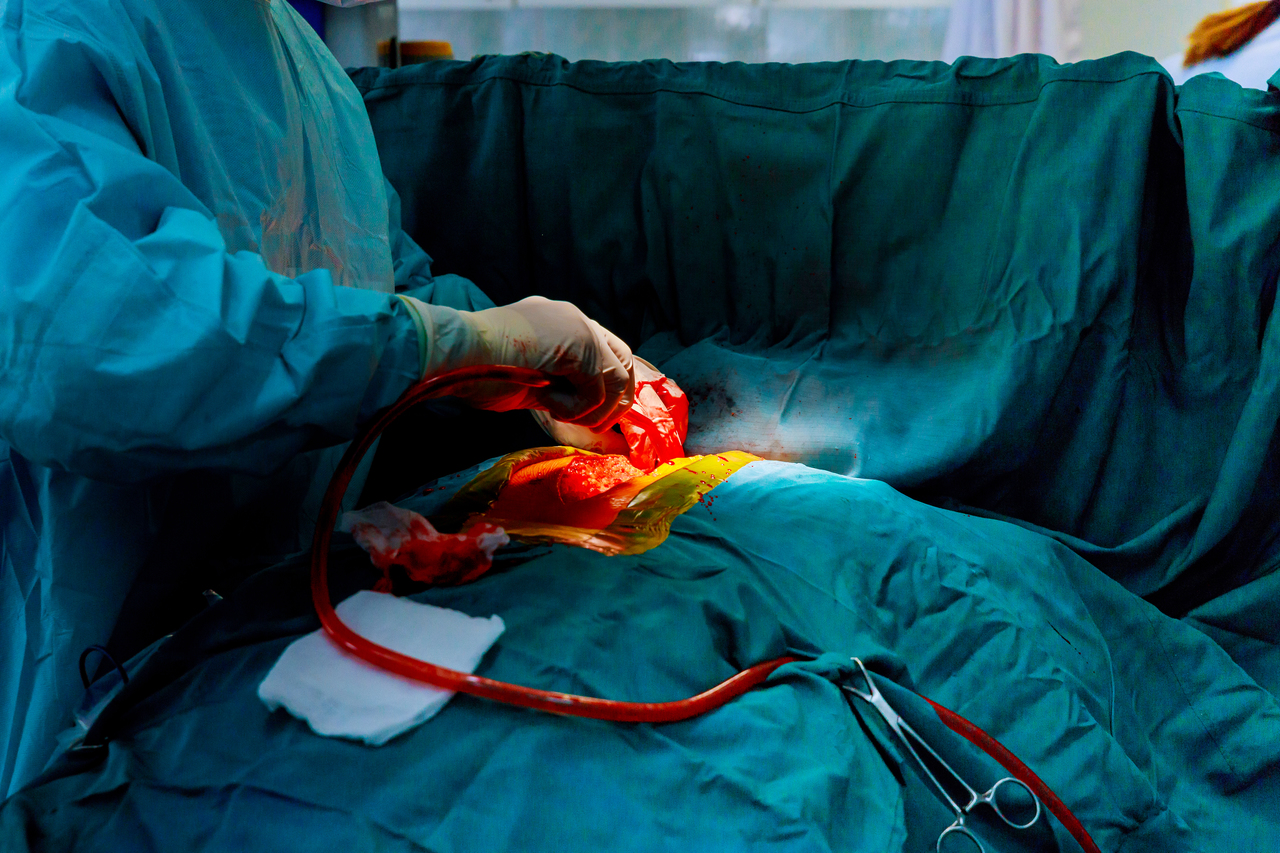

Placing a stent does not require open surgery. It is a relatively simple and quick procedure that uses a small incision in the arm or leg to approach the affected arteries and veins. A small catheter is then pushed through the incision and inserted into the blocked artery. Doctors who perform this procedure get to monitor and see the whole process through a live x-ray feed. It is much less invasive and the recovery and downtime are a lot shorter compared to the months required for you to heal from bypass surgery. After a stent procedure is done, you will be monitored for a short number of days and may be able to return to work and your normal routine.

A stent procedure can immediately improve blood flow throughout the body’s arteries. The moment the catheter reaches the damaged and blocked area of the artery, it will be placed in such a way that it restores the blood flow back to normal.